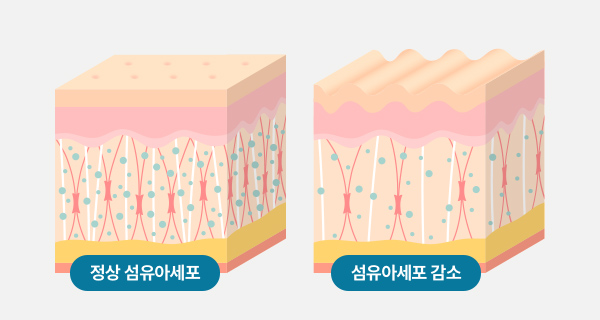

노화가 진행되면 섬유아세포와 콜라겐의 활성과 텐션이 감소되어

탄력 감소, 주름, 피부 색변화, 볼륨 감소 등이 발생됩니다.

섬유아세포와 콜라겐의 활성도와 텐션이 점차 감소됨

탄력감소, 주름증가, 볼륨이 감소된 피부